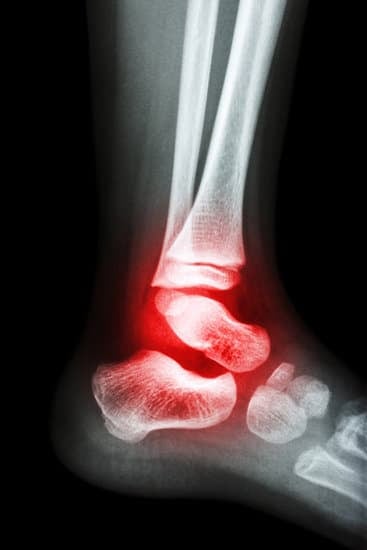

발목 관절염: 원인, 증상, 치료 및 관리

발목 관절염(Ankle Arthritis)은 발목 관절에 염증이 발생하여 통증과 부종, 관절의 움직임 제한을 일으키는 질환입니다.

이는 발목 관절의 연골이 손상되거나 마모되어 발생하며, 가장 흔한 형태로는 골관절염이 있습니다.